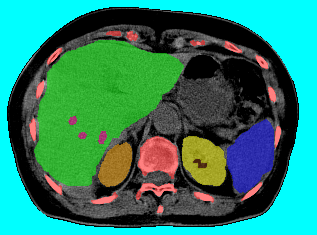

Abdominal Organ Segmentation:

We used CT dataset and extended the work in [13] which used Hedgehogs to segment liver and kidneys. In contrast to [13], we utilized more detailed structures reaching labels.

For each test case we computed the weighted precision

where is the ground truth labeling. The weighted recall is defined similarly. As shown in Table 3, all methods performed comparably due to the use of Hedgehog priors and the star-like structure of , which -exp is well suited for. See Table 4 for results without using Hedgehog priors. Figure 18 shows the tree and our result for one test case. Interestingly, QPBO labeled all the pixels in all 7 test cases. By comparing Tables 3 and 4 it is easy to see the benefit of using Hedgehog priors. Moreover, Path-Moves outperformed QPBO and a-exp after dropping the Hedgehog priors.

|

| (a) tree | |